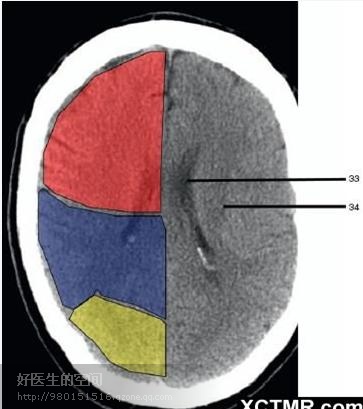

33、侧脑室体部 (Body of lateral ventricle) 34、放射冠 (Corona radiata) 浅红色部分为额叶(Frontal Lobe),黄色部分为枕叶(Occipital Lobe),褐色部分为顶叶(Parietal Lobe)